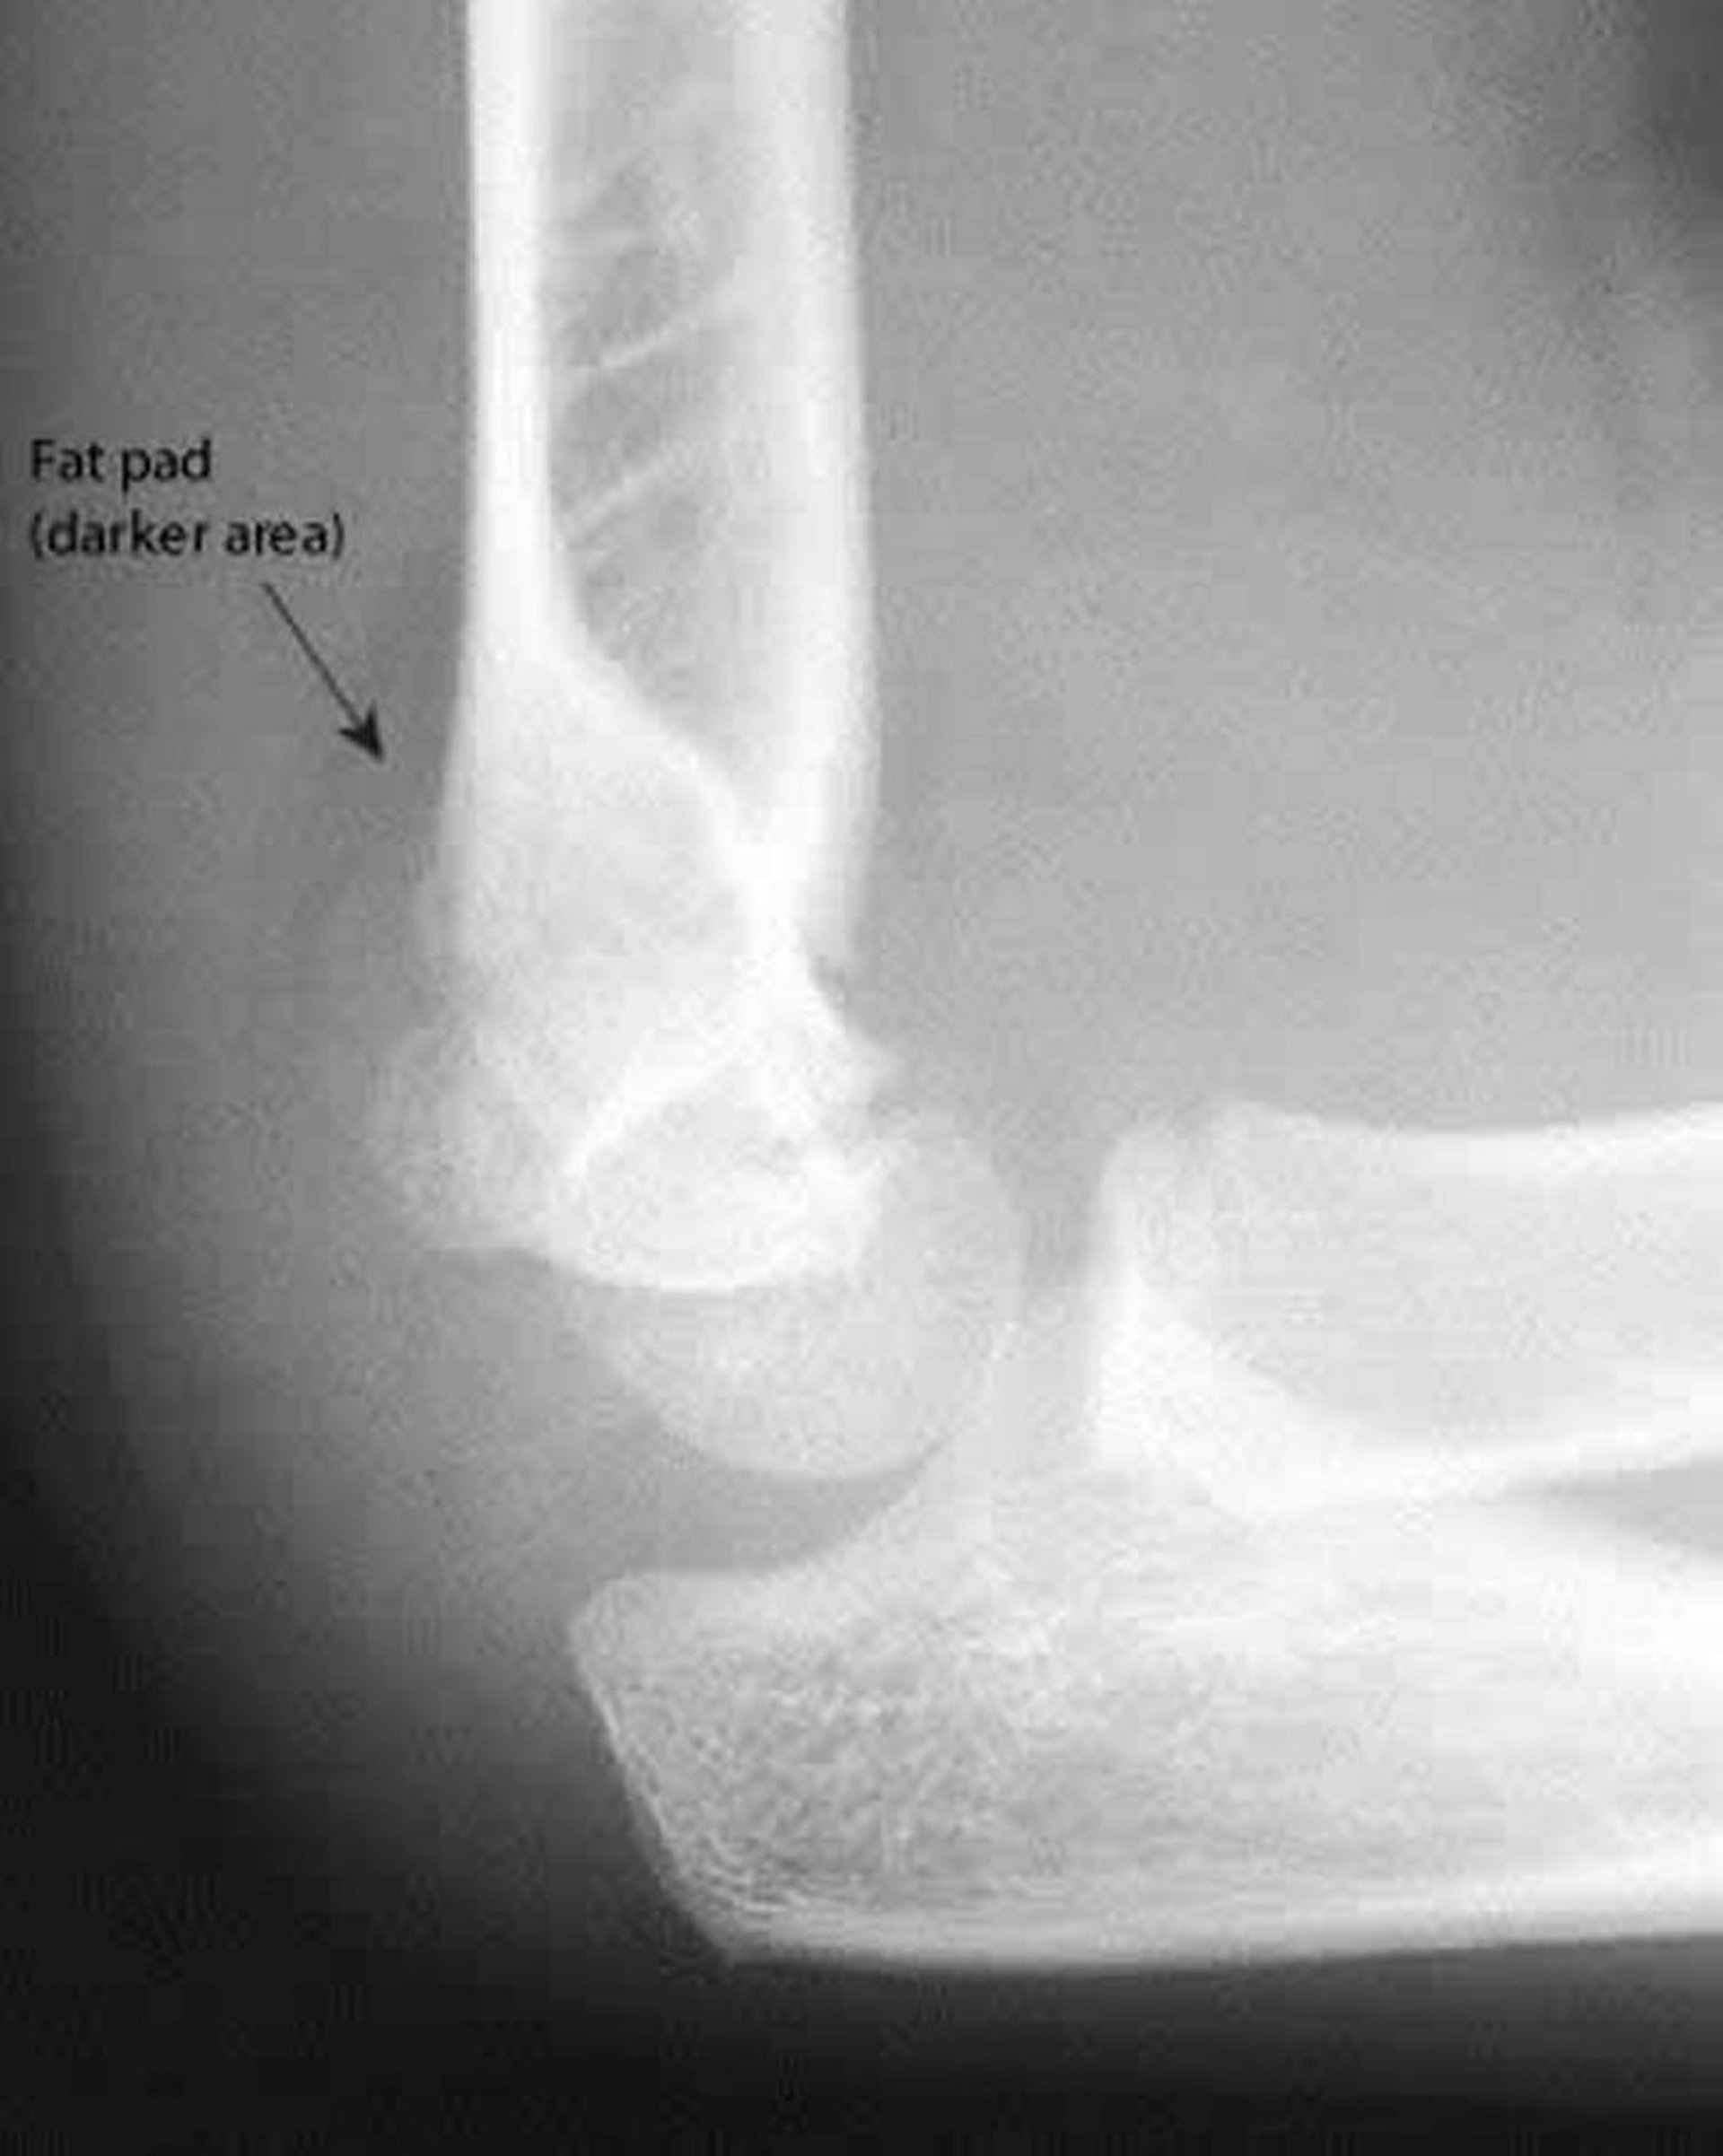

後方fat pad

後方fat padは常に異常である。またこのX線上では,anterior humeral lineが上腕骨小頭の中央を横断しない。

Image courtesy of Danielle Campagne, MD.